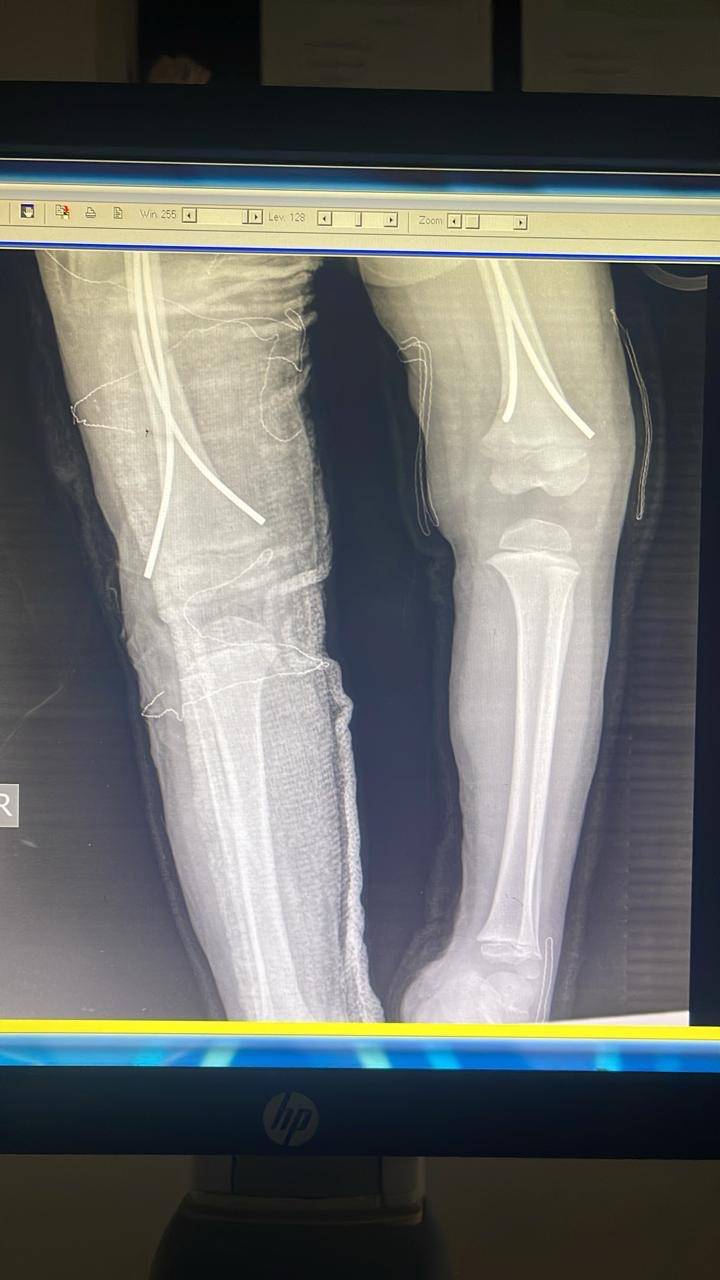

- إجراء عمليات جراحية معقدة و دقيقة في مجال العظام و المفاصل و الكسور و الإصابات ، رغم الضغط الكبير على المستشفى و أعداد المراجعين الكبيرة.

- تطبيق تقنيات جراحية حديثة و متقدمة، و ذلك في ظل التحديات التي يواجهها الفريق بسبب أعداد المرضى و المراجعين الكبيرة.